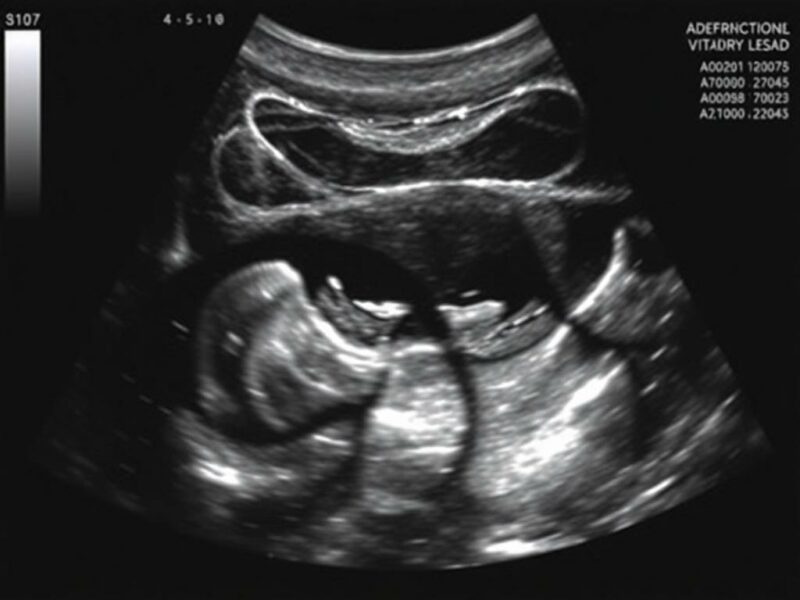

La técnica se adapta al objetivo. En el paciente agudo inestable, realizar una exploración dirigida FAST (Focused Assessment with Sonography for Trauma) o EFAST (Extended FAST) es prioritario: buscar líquido libre en perihepático, periesplénico, pelvis y espacio pericárdico, y, en EFAST, evaluar neumotórax mediante línea pleural y deslizamiento. En pacientes no traumáticos con dolor abdominal, la exploración completa incluye evaluación de hígado, vesícula biliar, vía biliar, páncreas (cuando sea posible), bazo, riñones y vejiga, y el examen de la aorta abdominal para descartar aneurisma o ruptura.

Técnicamente, registra imágenes en planos longitudinal y transversal de cada órgano; documenta medidas (p. ej., diámetro máximo de aorta), localiza y describe cualquier líquido libre (sacos de Morison, fondo de saco de Douglas), y evalúa signos dinámicos (peristalsis, compresibilidad de la vesícula, movimiento del epiplón). No olvides usar Doppler cuando haya sospecha de torsión, isquemia o trombosis; el Doppler color y pulsátil aportan información vascular fundamental.

Interpretación de hallazgos agudos: líquido libre, hemorragia y colecciones

El hallazgo de líquido libre en un paciente agudo puede cubrir un abanico etiológico: hemoperitoneo tras traumatismo, ascitis por patología hepática, líquido inflamatorio por perforación intestinal o derrame seroso en procesos inflamatorios. Es importante describir su localización (Morison, pelvis, periesplénico), cantidad aproximada (focal, moderada, abundante) y características ecográficas (anecogénico, con ecos internos indicativos de coágulos o pus).